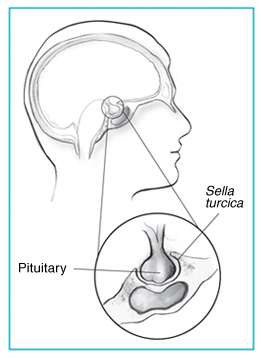

Sella turcica and pituitary gland. | |

The sella turcica (Latin for Turkish seat) is a saddle-shaped depression in the body of the sphenoid bone of the human skull and of the skulls of other hominids including chimpanzees, orangutans, and gorillas. It serves as a cephalometric landmark. The seat of the saddle, the deepest part of the sella turcica known as the hypophyseal fossa, holds the pituitary gland (hypophysis).

The seat of the saddle, the deepest part of the sella turcica known as the hypophyseal fossa holds the pituitary gland (hypophysis). The sella turcica is located in the sphenoid bone behind the chiasmatic groove and the tuberculum sellae. It belongs to the middle cranial fossa.[1] In front of the hypophyseal fossa is the tuberculum sellae.

The sella turcica forms a bony seat for the pituitary gland.